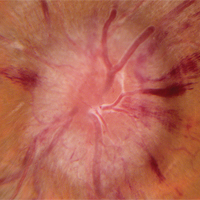

Ophthalmic PathologyImage

Assistant Professor and Director, Section of Ophthalmic Pathology

Richard J. Grostern, MD is fellowship trained in ocular pathology and oversee the department's clinical and educational pathology program. The resident laboratory experience takes place during the first year. Each first-year resident participates in two three-month rotations on the ophthalmic pathology service. Residents evaluate gross specimens and prepare them for fixation. Additionally, there are formalized one-on-one teaching with Dr. Grostern in the pathology lab. Although the volume of specimens derived from Rush patients is sufficient for the educational experience, additional unknown cases from the Ocular Pathology Library fortify the rotation. Dr. Grostern serve as ocular pathologist for the Cook County Medical Examiner. Emergency specimens can be processed and reviewed on virtually any day by the team. There is a one-hour block each month to conduct a pathology conference with the residents in morning didactic conferences.